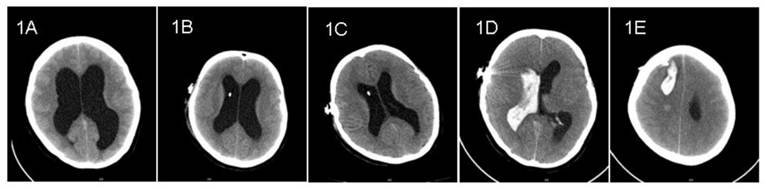

Case 1: A 32-year-old female complained of headache and dizziness for 2-month duration. Computed tomography (CT) showed markedly enlarged ventricles (Figure 1A). There were no space-occupying lesions on magnetic resonance imaging (MRI). Lumbar puncture revealed transparent CSF with an initial opening pressure of 255 mm H2O. A diagnosis of hydrocephalus was made and a VP shunt undertaken with a Medtronic Strata Programmable Valve System (pressure level, 2.5). Preoperative laboratory evaluation showed a normal prothrombin time (PT). The patient was not receiving anti-platelet or anti-coagulation medication. The VP shunt was inserted at the first attempt; no blood was observed in the CSF on ventricular cannulation. The patient recovered well and routine follow-up CT on postoperative days 1 and 3 showed collapsing ventricles without evidence of hemorrhage (Figure 1B, 1C). On postoperative day 5, the patient suddenly developed a headache and dizziness while urinating. Soon thereafter, the patient became unconscious; CT showed a large hematoma along the path of the ventricular catheter associated with an appreciable intraventricular hemorrhage (Figure 1D, 1E). Unfortunately, the patient died suddenly before evacuation of the hematoma was possible.

Figure 1

Pre- and post- operative CT imaging of case 1. 1A: Preoperative CT showed enlarged ventricles. 1B and 1C: CT showed shrinking ventricles on postoperative days 1 and 3. 1D and 1E: CT on postoperative day 5 showed intraventricular hemorrhage and intracerebral hematoma along the path of ventricular catheter.